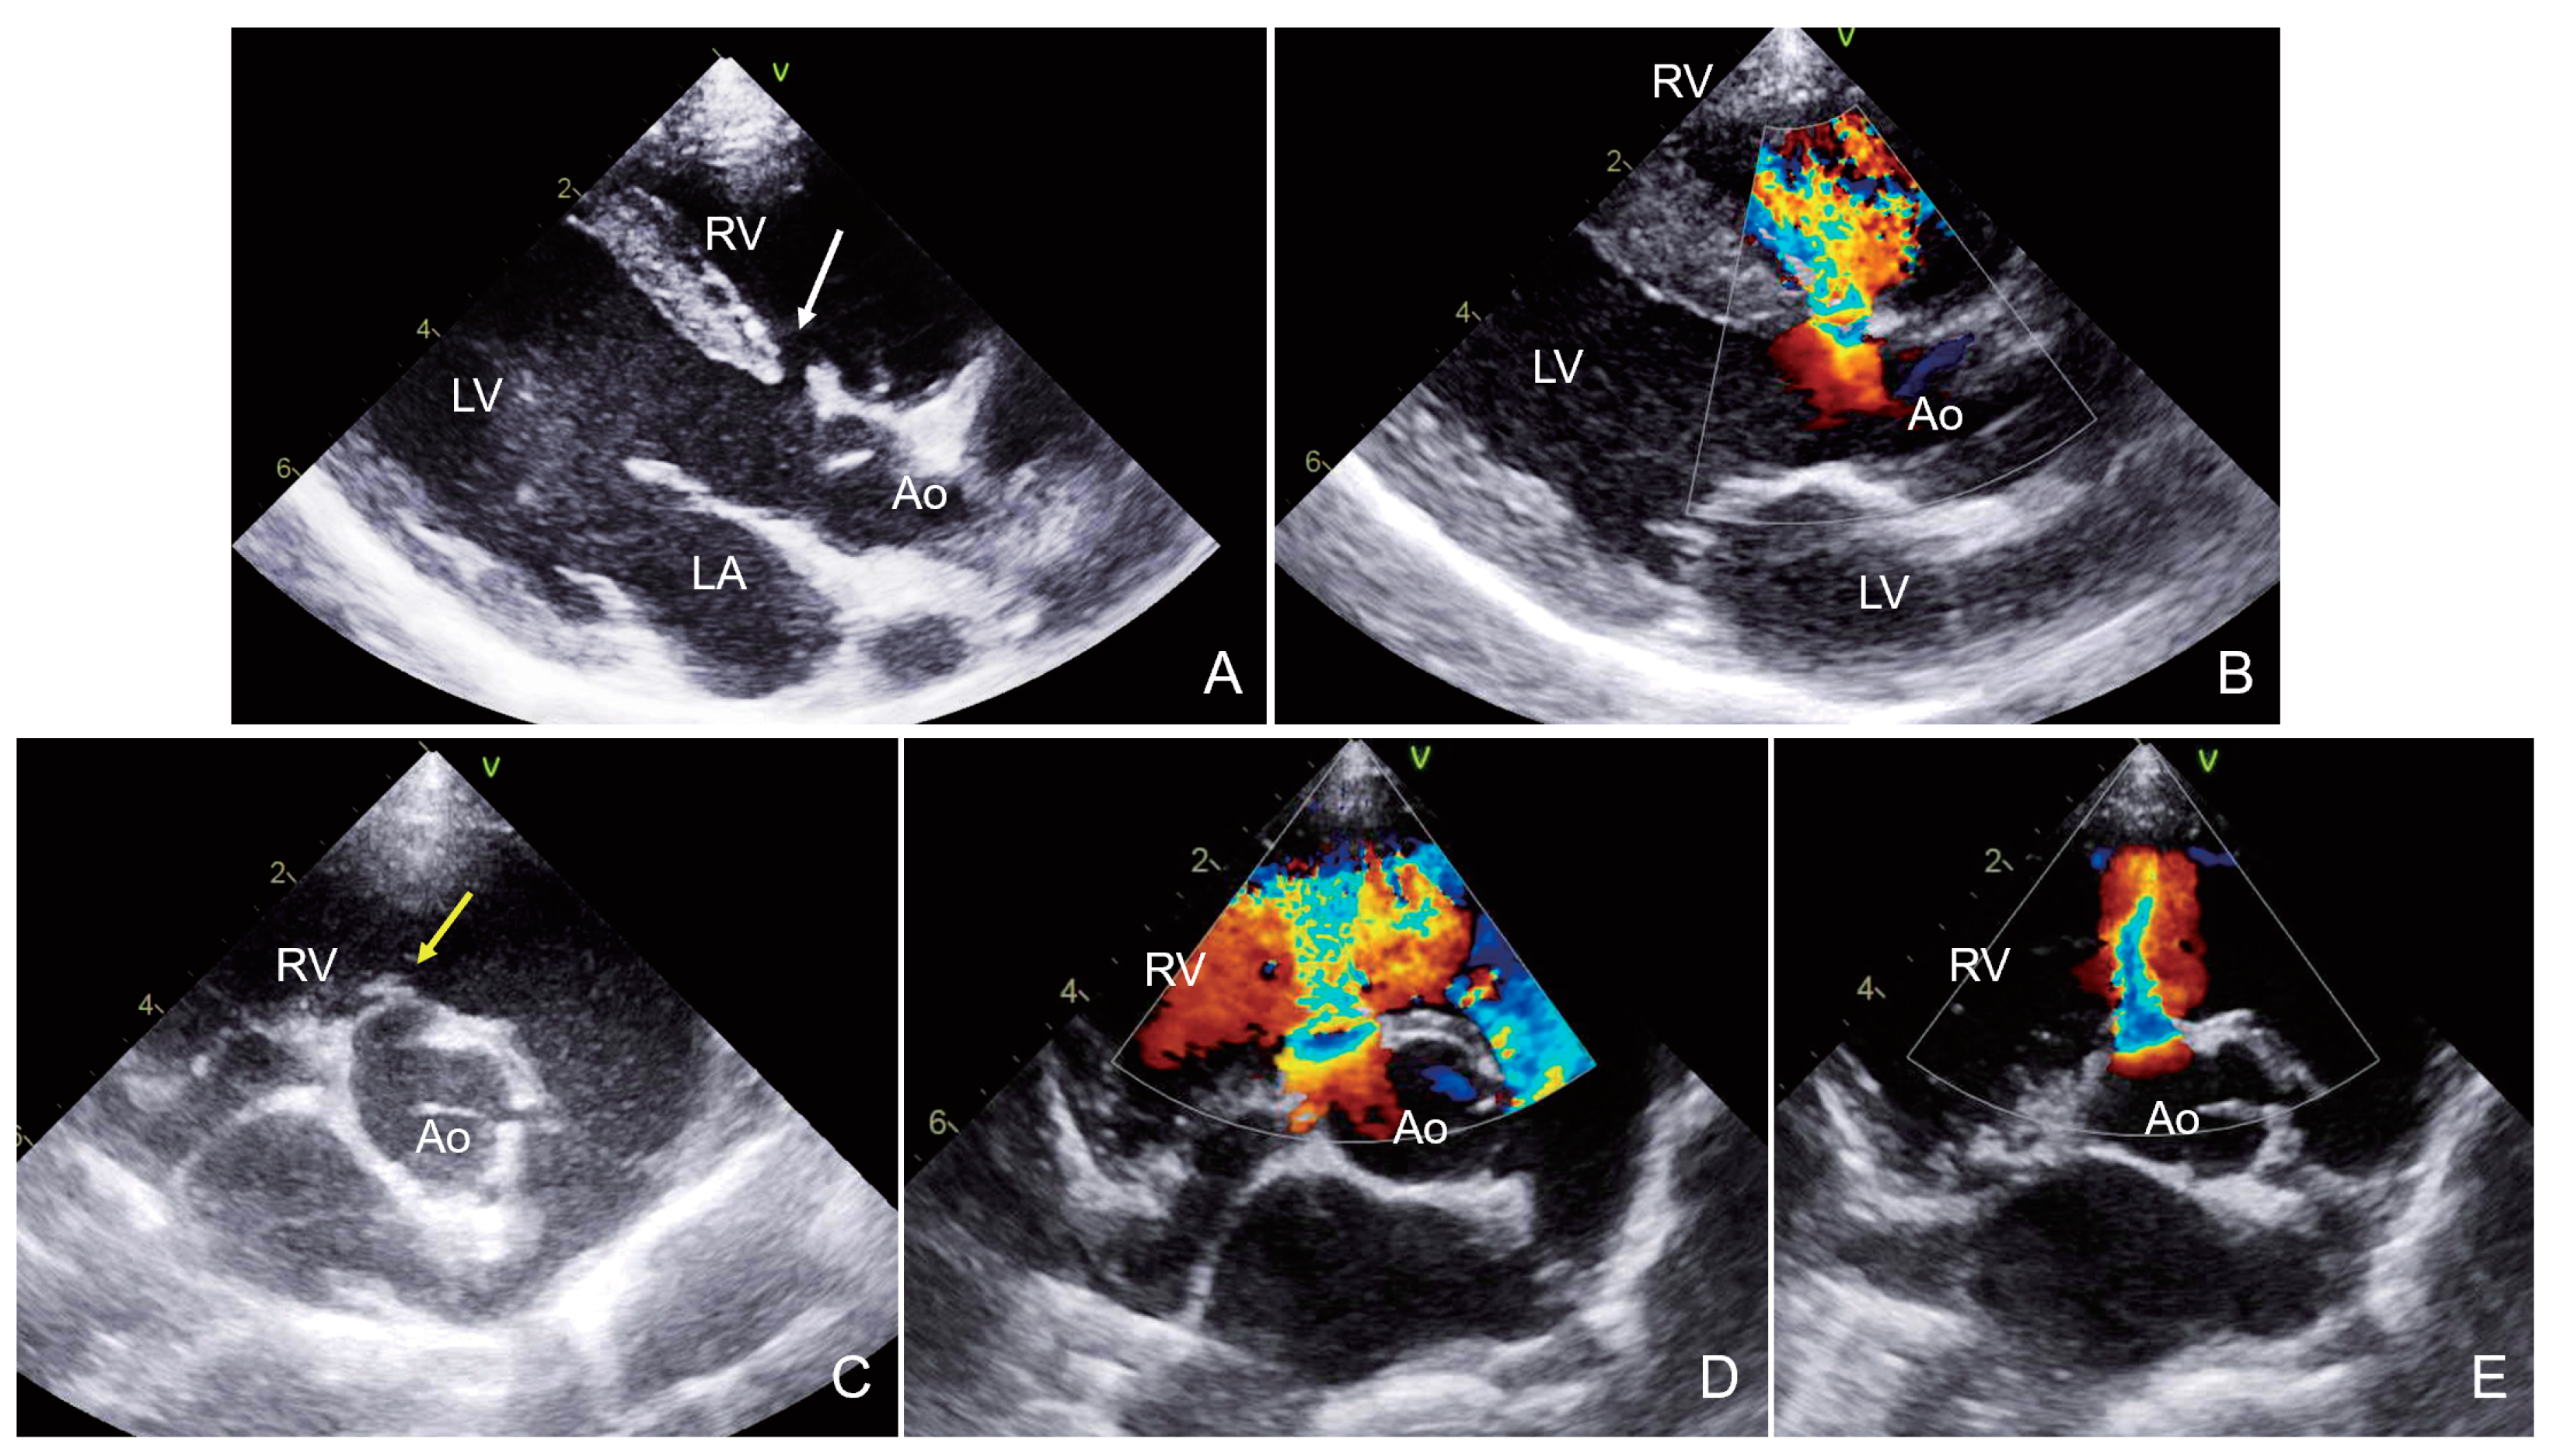

2.2. Case 2